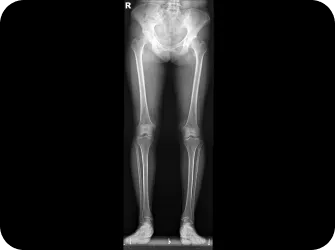

다리길이 엑스레이 검사

근육과 근막의 정렬을 함께 진단하며, 풀 스파인 촬영을 통해 머리부터 모든 고관절, 발의 정렬까지 함께 파악하여 개개인에 맞는 전신 치료법을 설계합니다.